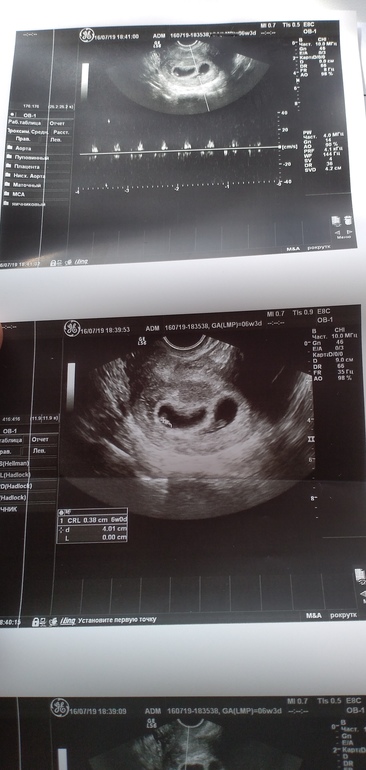

Фото с 1 узи

Подсадили 2 эмбрионов. Оба прижились(у каждого был свой ж. мешочек). 1эмбриончик прикрепился по передней стенке, 2-по задней. Было 2 узи. На первом ставили ди ди двойню. Позавчера на 2 узи(1скрининг) поставили Моно ди(общая плацента с перегородкой) . Как так получилось!?! Из ди ди в Моно ди!?! Плацента срослась?! Правда ли, что Моно ди всегда однополые и похожи между с собой!?!

Спасибо за ответ... Я прикрепила фото с 1 узи... Там видно, что 2 разных плода.... А врач во все горло утверждает, что это Моно, однояйцевые... По другому и быть типо не может... 💐💐💐💐

Спасибо за ответ.... А то я всю голову уже сломала... Либо я полная дура и считаю, что у меня ди ди... Либо врач 🙈🙊я и фото прикрепила, с 1 узи